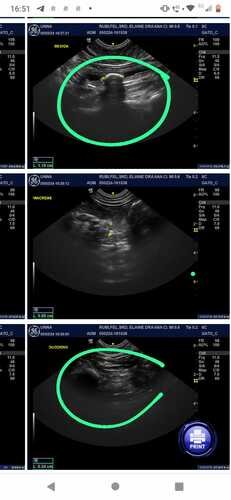

Infelizmente, a Rubi foi diagnosticada com cistolitíase (pedra na bexiga de grande proporção) e precisa realizar com urgência a retirada do cisto, isso custará R$ 800, 00 mais medicações e no momento não temos condições de pagar. Como membros da nossa comunidade felina, sabemos que vocês entendem o vínculo especial que compartilhamos com nossos animais de estimação. Qualquer contribuição, por menor que seja, fará uma enorme diferença para garantir que ela receba o tratamento de que precisa.